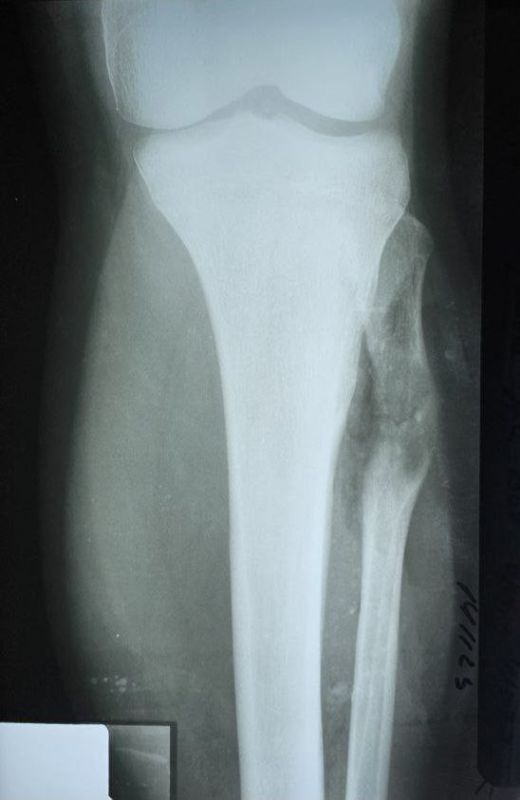

Донецкие врачи удалили подростку объемную опухоль кости14-летний подросток поступил в Республиканский травматологический центр (РТЦ) Минздрава ДНР с диагнозом «остеохондрома большеберцовой кости».Опухоль выдавила малоберцовую кость и разорвала...